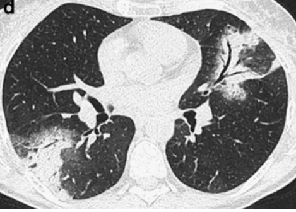

程大叔的胸部CT

程大叔来到某医院,医生给他做了一个胸部CT,结果却让他大吃一惊,CT提示:双肺多发结节,性质待定,考虑到程大叔 50多岁,长期抽烟,这可是妥妥的肿瘤高危人群啊,现在又是咳嗽又是胸痛的,难道真的是肺癌?